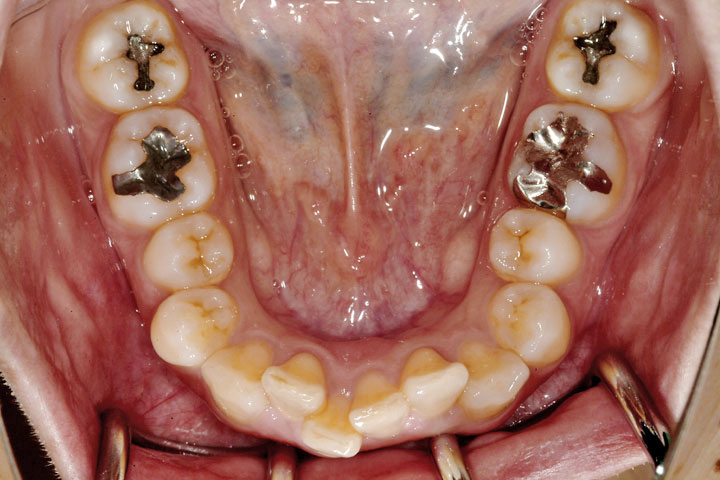

過蓋咬合(深いかみ合わせ)

叢生(乱ぐい歯)

かみ合わせの悪さを主訴に来院された成人女性の患者さんです。初診時は、下顎前歯が見えないほどのかみ合わせでしたが、何とか矯正治療で良い結果を得ることができました。エッジワイズ装置としてデーモンシステムを使い、約2年半の治療期間となりました。